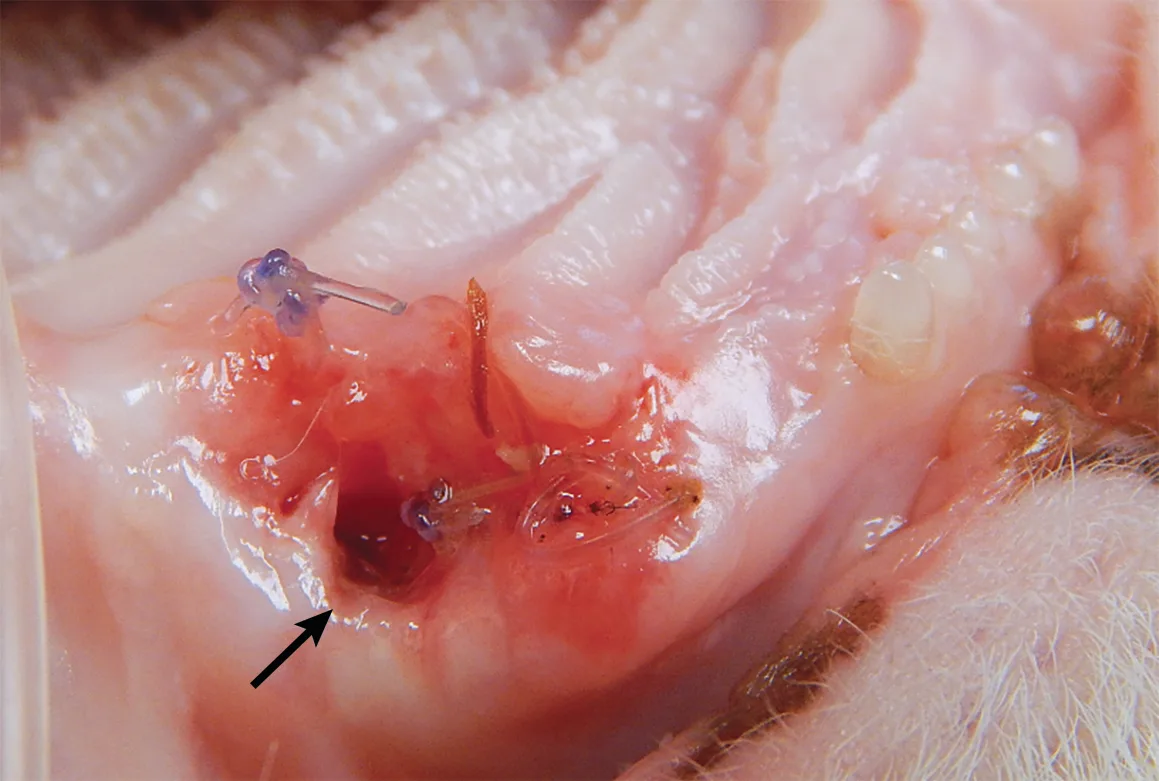

Closing a mucogingival flap under tension increases the risk for dehiscence,4 and understanding the options available for complete flap mobilization (eg, proper release of the periosteum, preplanning advancement flap design, releasing incision placement) is important when reducing tension on a flap. Damaged tissue should be removed prior to closure of the wound. Patients with severe periodontal disease can have significant loss of the buccal-attached gingiva and mucosa (Figure 3). Tissue that is lost, either due to pre-existing disease or surgical trauma, makes closure of a gingival flap more difficult.

Calculus accumulation and significant loss of the attached gingiva (arrows) of the left maxillary canine tooth. Gingival recession can make surgical closure more difficult and increase the potential for postoperative complications.